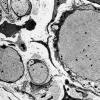

1B4 Disulfiram (Case 1) EM009 - Copy

1B5 Disulfiram (Case 1) EM011 - Copy

1B6 Disulfiram (Case 1, Image thanks to JM Bilbao) EM1 - Copy

1B7 Disulfiram (Case 1, image thanks to JM Bilbao) EM6 - Copy